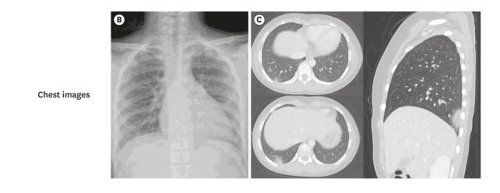

서울대병원 소아청소년과 최은화 교수·분당서울대병원 소아청소년과 박지영 교수 연구팀이 국내 첫 어린이 코로나19 환자 임상 증상 및 치료 경과 등을 담은 논문을 보면, 이 환자는 확진 3일 전부터 약간의 가래 증상이 보고됐지만, 설사나 구토 등 증상은 없었다. 흉부 컴퓨터단층촬영(CT)에서 가벼운 폐렴이 확인됐으나 항바이러스제를 투여할 수준은 아니었다.